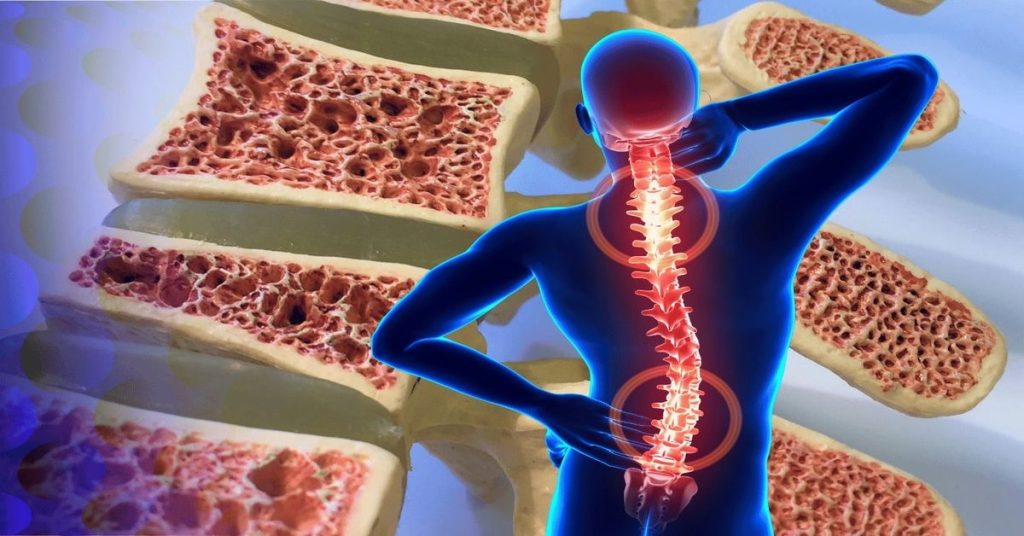

İleri yaş döneminde hastalık sessiz şekilde ilerleyebilir. Omurga, kalça ve el bileği kırıkları en sık görülen sorunlar arasındadır. Boy kısalması ve sırt ağrısı da görülebilir. Bazı kişilerde duruş bozukluğu ortaya çıkabilir. Hastalık ilerledikçe omurgada çökme kırıkları oluşabilir. Bu durum günlük yaşam aktivitelerini zorlaştırabilir. Bu nedenle erken tanı ve düzenli kontroller, kemik erimesi riskinin kontrol altında tutulması açısından büyük önem taşır.

İleri yaşta görülen kırıkların önemli bir nedeni kemik erimesi olabilir. Özellikle kalça, omurga ve el bileği kırıkları sık görülür. Bazı kişilerde boy kısalması ve sırt ağrısı ortaya çıkabilir. Duruş bozukluğu zamanla belirgin hale gelebilir. Hastalık ilerledikçe günlük hareketler zorlaşabilir. Bu nedenle erken tanı ve düzenli takip büyük önem taşır. Kemik yoğunluğu ölçümleri risk durumunu belirlemede yardımcı olabilir.

Kemik yoğunluğunun azalması sonucu kemikler daha kırılgan hale gelir. Bu durum özellikle ileri yaşlarda kırık riskini artırır. Hastalar çoğu zaman sorunu kırık oluşana kadar fark etmeyebilir. Bu nedenle erken tanı büyük önem taşır. Kemik sağlığını korumak için düzenli kontroller yapılmalı ve risk faktörleri erken dönemde değerlendirilmelidir. Tedavi planı her hastanın ihtiyaçlarına göre hazırlanır ve süreç uzman kontrolünde yürütülür.

Tedavi sürecinde kemik erimesi için farklı yöntemler uygulanabilir. Kalsiyum ve D vitamini desteği kemik yapısını güçlendirmeye yardımcı olabilir. Doktor kontrolünde kullanılan bazı ilaçlar kemik kaybını yavaşlatabilir. Düzenli egzersiz programları kasları ve kemikleri güçlendirebilir. Özellikle yürüyüş ve denge egzersizleri düşme riskini azaltabilir. Tedavi planı kişinin yaşı, kemik yoğunluğu ve genel sağlık durumuna göre belirlenir.